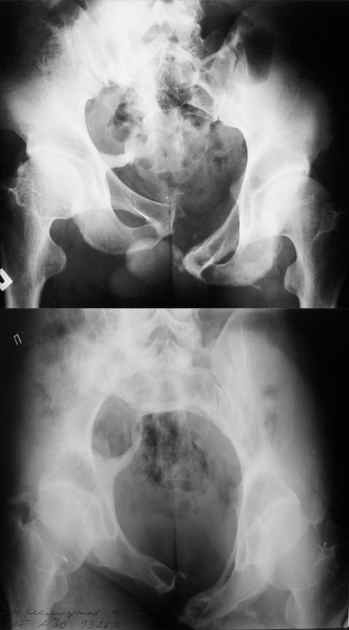

Маленькая иллюстрация (около 5 лет после травмы). Результат плохой -

укорочение, хромота, периодически боли в спине, но больной отказывается

от операции, видимо, не так все трагично.